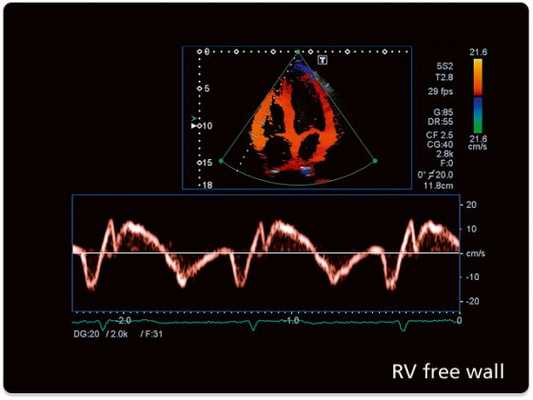

На сегодняшний день наиболее широко применяемым исследованием при помощи допплера является тканевая методика. Данный метод оптимизирован для изучения не только направления кровотока, но и визуализации движений сердечных тканей. В ходе допплеровского анализа происходит окрашивание миокарда в различные цвета в соответствии со скоростью и направленностью кровяного потока. Технику применяют для выявления локализованных изменений в сократительной функции миокарда. Данные, получаемые в ходе анализа, регистрируются в виде графика, отображающего зависимость скорости от времени.

С помощью тех же или дополнительных датчиков выполняется допплеровское исследование, основанное на измерении частотного сдвига возвращенного сигнала, что позволяет определить скорость и направление движения потоков крови внутри сердца и крупных сосудов (например, через аортальный клапан) или самого миокарда (тканевая допплерография).

- Измерение скоростей входящего митрального потока, времени его замедления, параметров кровотока в легочных венах и тканевая допплерография в области кольца митрального клапана позволяет достаточно точно оценить диастолическую функцию ЛЖ, включая давление наполнения ЛЖ.